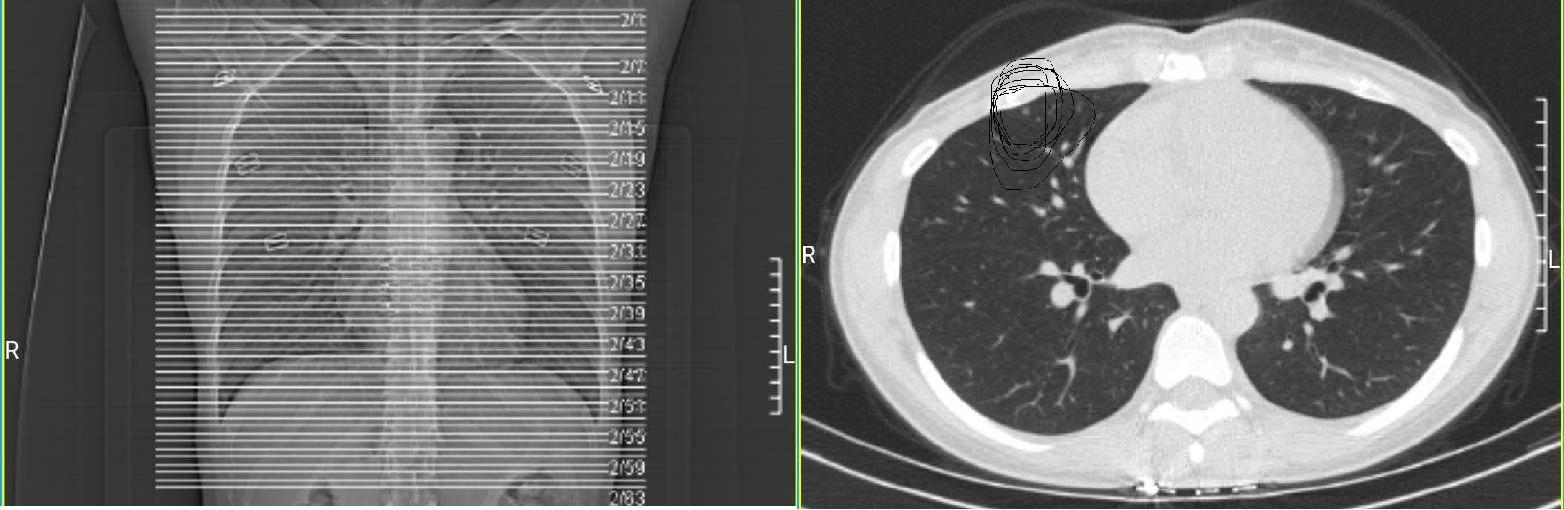

胸片是通过机器发出X射线穿透人体之后被探测器捕捉,并得到了一副透视胸部的平面图像。而CT是多层螺旋扫描,把脏器的分层扫描得出多副图像(分多少层,就能得到多少副图像)。CT扫描的好处在于不仅可以分层检查脏器,还可以通过不同的角度旋转三维重建观察病灶特征。而拍片是平面图,达不到CT的三维效果及病灶的准确位置。例如下图胸片以及胸部CT,其中胸片中专门画出来很多横线,代表CT切的每个层面。